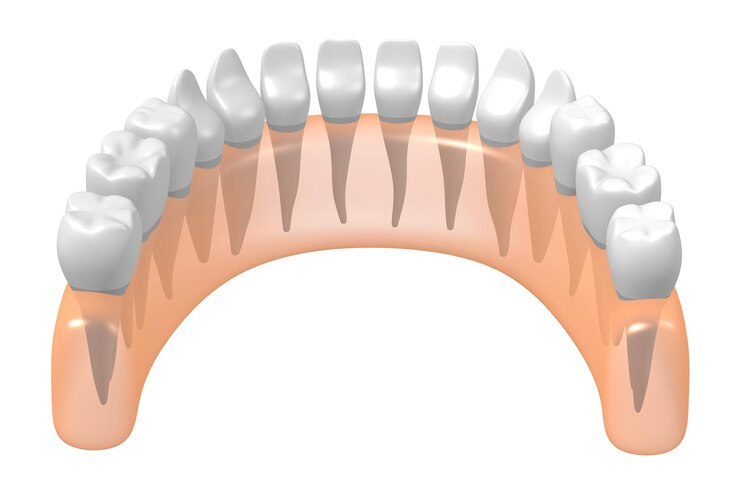

Dental crowns are tooth-shaped caps that are placed over damaged or decayed teeth to restore their shape, size, and strength. If your dentist recommends a dental crown, it is important to understand what to expect during the procedure.

- After the tooth has been cleaned and prepared, your dentist will shape it to prepare it for the crown. This may involve removing additional material from the tooth to ensure that the crown fits properly.

- Next, your dentist will take impressions of the tooth to create a custom-made crown. These impressions will be used to create a mold of the tooth, which will then be sent to a dental laboratory where the crown will be made.